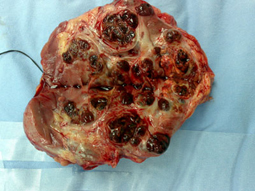

فريق طبي ينجح في استئصال ورم من سيدة ثمانينية بمستشفى الأمير سلمان

تمكن فريق طبي جراحي بمستشفى الأمير سلمان بن عبدالعزيز بإنقاذ حياة مريضة بعد أن أجرى عملية استئصال ورم خبيث من الكلية اليسرى لمريضة سعودية، وكانت المريضة والتي تبلغ من العمر ثمانين عاماً تعاني من تبول دموي وتم تشخيصها عند الدخول بعمل أشعة فوق الموجات الصوتية أظهرت وجود ورم بالكلية اليسرى فتم عمل الفحوصات اللازمة من أشعة مقطعية وأشعة رنين مغناطيسي والتي أظهرت أن الورم قد انتشر في الكلية اليسري مدمرا معظم أنسجة الكلية اليسرى وانتشر لحوض الكلية مما أدى إلى نزيف يومي متواصل مع تكون جلطات دموية بالمثانة والبول فنتج هذا عن فقر دم شديد وتم نقل العديد من وحدات الدم للمريضة أثناء فترة العيد ولعدم وجود قبول من المراكز المتخصصة لعمل إغلاق الشريان المؤدي للكلية عن طريق القسطرة الشريانية وتفريغ الخثرة الدموية الممتدة عبر الوريد الكلوي والوريد الأجوف العلوي.

الجراحية وقام بإجراء العملية الفريق الطبي المكون من الدكتور عتيق بن محمد القرني استشاري جراحة المسالك البولية والدكتور محمد أبو النصر استشاري جراحة المسالك البولية والدكتور حسام صالح وقد تعافت المريضة من الجراحة ولله الحمد.